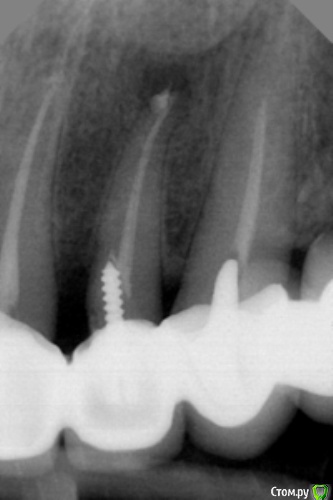

dr.Dre Опубликовано 16 января, 2017 Поделиться Опубликовано 16 января, 2017 Добрый день уважаемые коллеги,пациентка 40 лет ,вверх полностю дуга керамики ,до своего доктора кто ето сделал возвращаться не хочет , в наличии есть микроскоп ,реально ли сделать не снимая дуги. Ссылка на комментарий

DrNice Опубликовано 16 января, 2017 Поделиться Опубликовано 16 января, 2017 Добрый день уважаемые коллеги,пациентка 40 лет ,вверх полностю дуга керамики ,до своего доктора кто ето сделал возвращаться не хочет , в наличии есть микроскоп ,реально ли сделать не снимая дуги.Задавались недавно мои терапевты таким вопросом, пришли к выводу что основная проблема - металический каркас, который будет давать погрешность на апексе. КТ есть? Хотелось бы увидеть положение анкера. Ссылка на комментарий

vse32 Опубликовано 16 января, 2017 Поделиться Опубликовано 16 января, 2017 Сложно, но реально. Если от коронки только стенки оставить. Аплок ведет себя нормально если изолировать каркас фумкой. Вопрос в положении анкера. КТ было бы здорово увидеть.А по факту делала такое пару раз.1. На временной полной дуге - снимать побоялась, что сломается при снимании, а ортопед одномоментную времянку прямо на анкер посадил. Не просек. 2. Раз на реальных коронках, но подлежащих снятию. Готовила под новое протезирование. То есть раздолбанная коронка потом снялась. Ссылка на комментарий

dr.Dre Опубликовано 16 января, 2017 Автор Поделиться Опубликовано 16 января, 2017 в чем заключаются жалобы ? симптоматика есть? У вас есть неплохой шанс сделать ещё хуже. на десне был свищ,боли как при гранулёматозном периодонтите Ссылка на комментарий

Kolchanov Опубликовано 16 января, 2017 Поделиться Опубликовано 16 января, 2017 Там легко может быть перфа от штифта, а если и нет, то запросто трещина может образоваться при вытаскивании. Добавьте сюда уже имеющийся там кариес, отсутствие культи под коронкой после лечения, возможные сколы керамики, гипохлорит во рту пациента (у вас не рвало пациентов в коффере? у меня было) и определитесь, так ли вы хотите помочь этому человеку.. 2 Ссылка на комментарий

DrNice Опубликовано 16 января, 2017 Поделиться Опубликовано 16 января, 2017 новую коронку как когда ето дуга Сепарация этой коронки от дуги, реэндо, моделировка культевой части, коронка. Это как один из вариантов, если все пойдет хорошо. Если все пойдет плохо, опять таки сепарация. Но для начала КТ, надо понимать положение анкера. Ссылка на комментарий